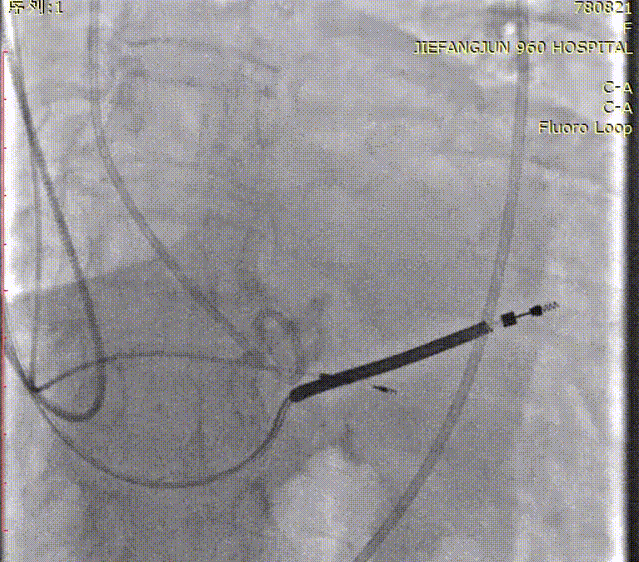

导丝成功跨瓣后,送入18mm Prizballoon®球囊成功通过主动脉瓣狭窄处,在180 bpm快速起搏下行球囊预扩张。

导丝跨瓣

球囊预扩